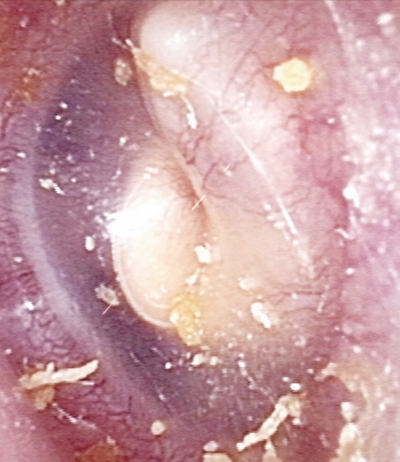

5歳女児の左鼓膜の写真を別に示す。治療として適切なのはどれか。

a. 抗菌薬投与

b. 鼓膜切開術

c. 鼓膜チューブ留置術

d. 鼓膜形成術

e. 鼓室形成術